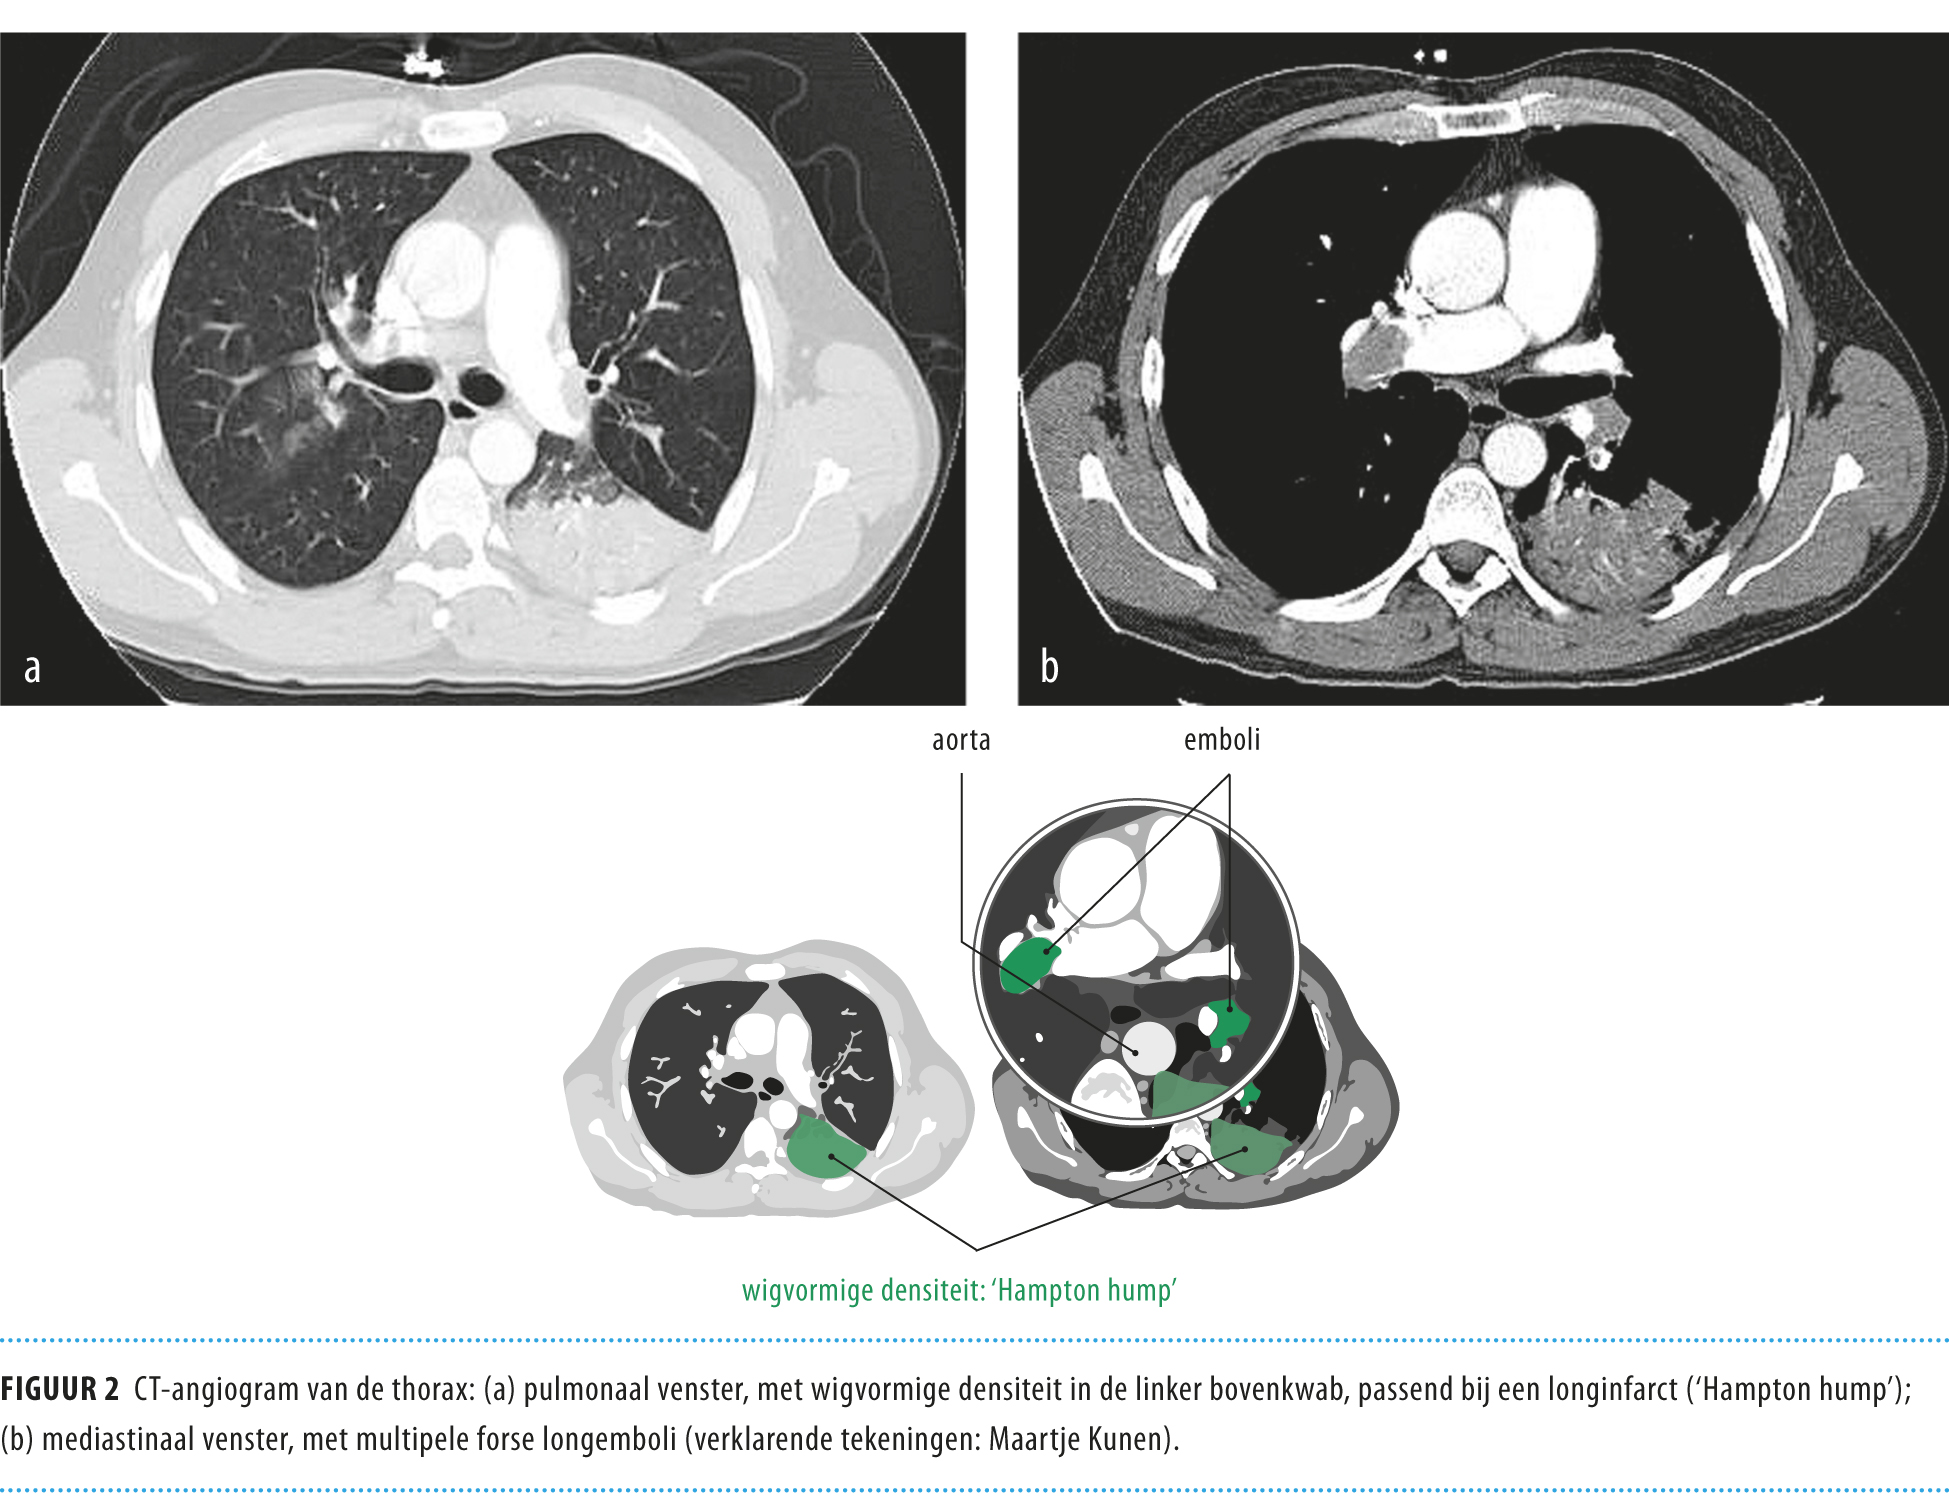

Subtle Pulmonary Embolism Left Upper Lobe - Chest Case ...

Subtle Pulmonary Embolism Left Upper Lobe - Chest Case ... from ctisus.com